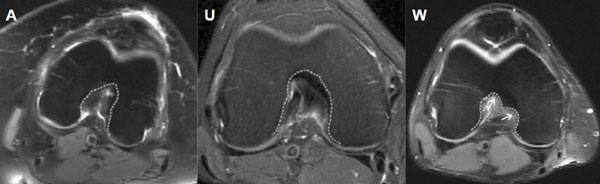

Las imágenes fueron presentadas en modo diapositivas a dos cirujanos artroscopistas, con más de diez años de experiencia. Previamente se entregó instructivo acorde con la bibliografía en relación al artículo de investigación de donde se tomó el protocolo (fig. 1), se solicitó completar una planilla seleccionando por cada corte de RM entre tres opciones: intercóndilo tipo U, tipo A, tipo W. El morfotipo A se interpreta como un intercóndilo estrecho desde la base hasta el ápex; el U donde no presenta un ahusamiento central con un mayor contorno respecto al tipo A; y el tipo W tiene las características del tipo U y dos ápices a nivel del vértice.

Figura 1: Cortes axiales de RM ejemplificando tres morfologías del intercóndilo.